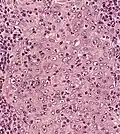

Micrograph showing a nasopharyngeal carcinoma positive for Epstein-Barr virus-encoded small RNAs (EBER).

NPC is caused by a combination of factors: viral, environmental influences, and heredity.[4] The viral influence is associated with infection with Epstein–Barr virus (EBV).[5][6] The Epstein-Barr virus is one of the most common viruses. 95% of all people in the U.S. are exposed to this virus by the time they are 30–40 years old. The World Health Organization does not have set preventative measures for this virus because it is so easily spread and is worldwide. Very rarely does Epstein-Barr virus lead to cancer, which suggests a variety of influencing factors.

The association between Epstein-Barr virus and nasopharyngeal carcinoma is unequivocal in World Health Organization (WHO) types II and III tumors but less well-established for WHO type I (WHO-I) NPC, where preliminary evaluation has suggested that human papillomavirus (HPV) may be associated.[11] EBV DNA was detectable in the blood plasma samples of 96% of patients with non-keratinizing NPC, compared with only 7% in controls.[6] The detection of nuclear antigen associated with Epstein-Barr virus (EBNA) and viral DNA in NPC type 2 and 3, has revealed that EBV can infect epithelial cells and is associated with their transformation. The cause of NPC (particularly the endemic form) seems to follow a multi-step process, in which EBV, ethnic background, and environmental carcinogens all seem to play an important role. More importantly, EBV DNA levels appear to correlate with treatment response and may predict disease recurrence, suggesting that they may be an independent indicator of prognosis. The mechanism by which EBV alters nasopharyngeal cells is being elucidated[12] to provide a rational therapeutic target.[12]